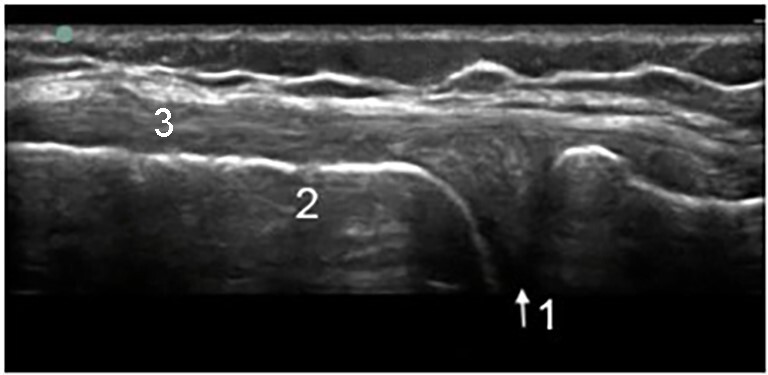

Knee Medial Collateral Ligament (MCL) and Medial Meniscus Image

1. Medial Meniscus

2. Femur

3. Medial Collateral Ligament (MCL)